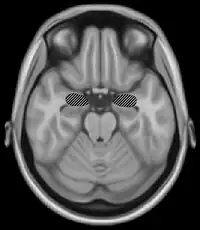

Basal ganglia and motor memory

The basal ganglia are a group of nuclei which are located in the medial temporal lobe, above the thalamus and connected to the cerebral cortex. Specifically, the basal ganglia includes the subthalamic nucleus, substantia nigra, the globus pallidus, the ventral striatum and the dorsal striatum, which consists of the putamen and the caudate nucleus.[8] The basic functions of these nuclei deal with cognition, learning, and motor control and activities. The basal ganglia are also associated with learning, memory, and unconscious memory processes, such as motor skills and implicit memory.[4] Particularly, one division within the ventral striatum, the nucleus accumbens core, is involved in the consolidation, retrieval and reconsolidation of drug memory.[9]

The caudate nucleus is thought to assist in learning and memory of associations taught during operant conditioning. Specifically, research has shown that this part of the basal ganglia plays a role in acquiring stimulus-response habits, as well as in solving sequence tasks.[8]

Damage to the basal ganglia has been linked to dysfunctional learning of motor and perceptual-motor skills. Most disorders that are associated with damage to these areas of the brain involve some type of motor dysfunction, as well as trouble with mental switching between tasks in working memory. Such symptoms are often present in those who suffer from dystonia, athymhormic syndrome, Fahr's syndrome, Huntington's disease or Parkinson's disease. Huntington's and Parkinson's disease involve both motor deficits and cognitive impairment.[8]